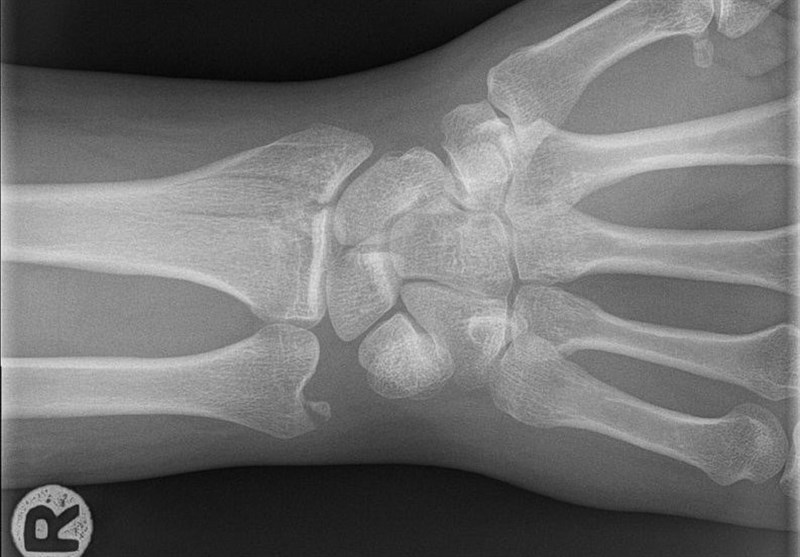

The second paper focused on identifying problems that require treatment. The issue the focused on is bone fractures. While these are often easy to spot, small chip or hairline fractures can be difficult for even a specialist to spot. And, in most cases, the diagnosis falls to a non-specialist, typically a doctor working in emergency medicine. The new research isn't intended to create an AI that replaces these doctors; rather, it's intended to help them out.

The team recruited 18 orthopedic surgeons to diagnose over 1,350,000 images of potential wrist fractures, and then it used that data to train their algorithm, a deep-learning convolutional neural network. The algorithm was used to highlight areas of interest to doctors who don't specialize in orthopedics. In essence, it was helping them focus on areas that are mostly likely to contain a break.

In the past, trials like this have resulted in over-diagnosis, where doctors would recommend further tests for something that's harmless. But in this case, the accuracy went up as false positives went down. The sensitivity (or ability) to identify fractures went from 81 percent up to 92 percent, while the specificity (or ability to make the right diagnosis) rose from 88 percent to 94 percent. Combined, these results mean that ER docs would have seen their misdiagnosis rate drop by nearly half.